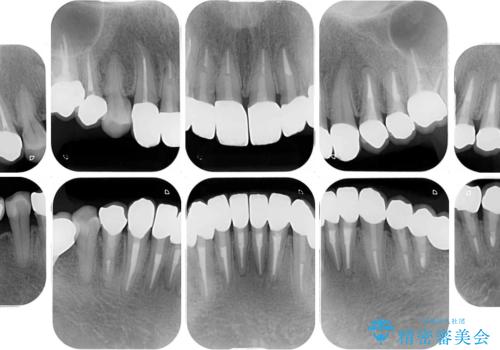

- 下顎の前歯に激痛を覚えて来院された患者様です。

取り急ぎ下顎前歯数歯の根管治療を、銀座しらゆり歯科医院長の林先生にお願いし、それ以外に気になっている、不自然な色調のクラウン、金属部分が見えてブラッシングがしにくいインプラント補綴、口元の突出感、出血のしやすい歯周ポケットなど、全てを解決するための治療を行うこととしました。

期間と費用はかかりましたが、気になっていた部分全てを改善でき、患者様には大変満足していただきました。